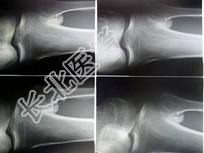

- 单项选择题女,22岁。反复头痛伴双下肢水肿10余年, 有多饮、多尿,近1个月来咳嗽, 呈阵发性,有时伴有脓痰, 低热,头部可触及柔软的软组织肿块及边缘不规则的骨缺损, 四肢及躯干皮肤可见散在出血点,双下肢凹陷性水肿, 结合所提供的图像,最可能的诊断是 ( )

A、韩-雪病

B、非骨化性纤维瘤

C、骨巨细胞瘤

D、骨纤维结构不良

E、内生软骨瘤